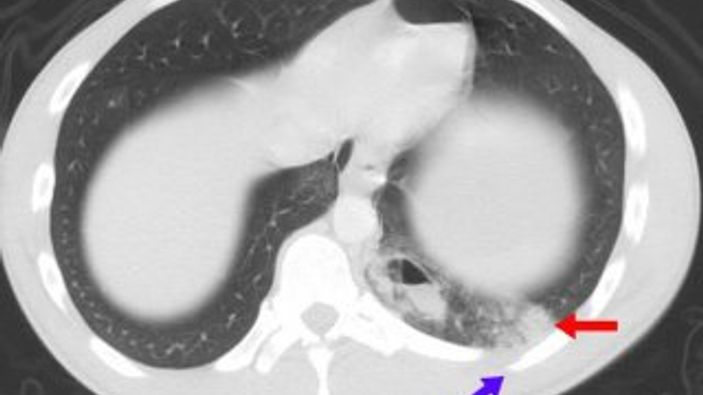

Asemptomatik olgularda hasta medikal testlere tabi tutulmazsa, hastalık ortaya çıkmaz (X-ray ve diğer tetkikler). Bazı kanserli hastalar uzun bir süre asemptomatik kalabilirler, böyle hastalarda ihtiyati önlemler alınmalıdır.